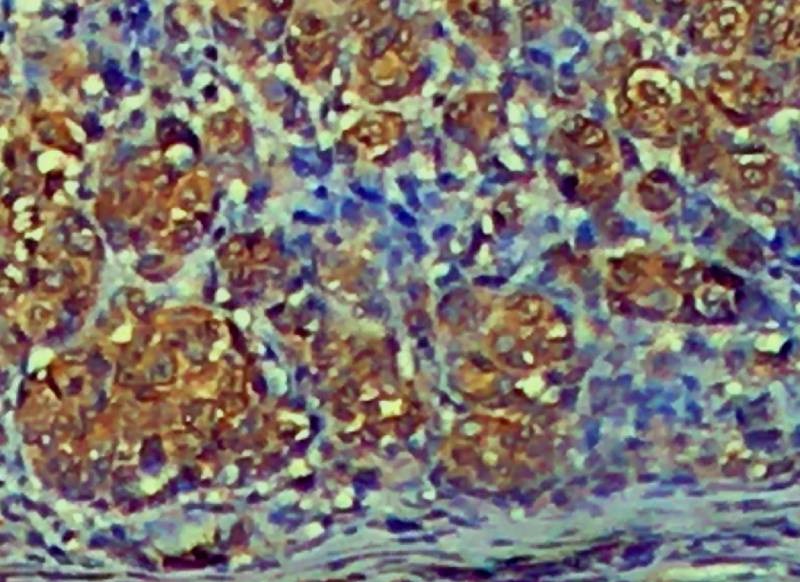

Anti-Arginase 1, Clone C-2

Arginase 1 (also known as liver type arginase or Type 1 arginase, ARG1) is a 35-40 kDa member of the arginase family of enzymes that catalyzes the breakdown of L-arginine into ornithine and urea. It demonstrates two distinct functions: it catalyzes the conversion of arginine to ornithine and urea in the hepatocyte cytoplasm, while in multiple cells, it degrades arginine, thus indirectly downregulating Nitric Oxide synthase activity by depriving this enzyme of its substrate. It is a highly expressed cytosolic enzyme in the liver and other tissues, including the brain. Arginase 1 also appears to play critical roles throughout the CNS for survival and regeneration of neurons and axons. Arginase 1 is an excellent marker for hepatocytes and used in differential diagnosis of Hepatocellular carcinoma from metastatic tumors of the liver.